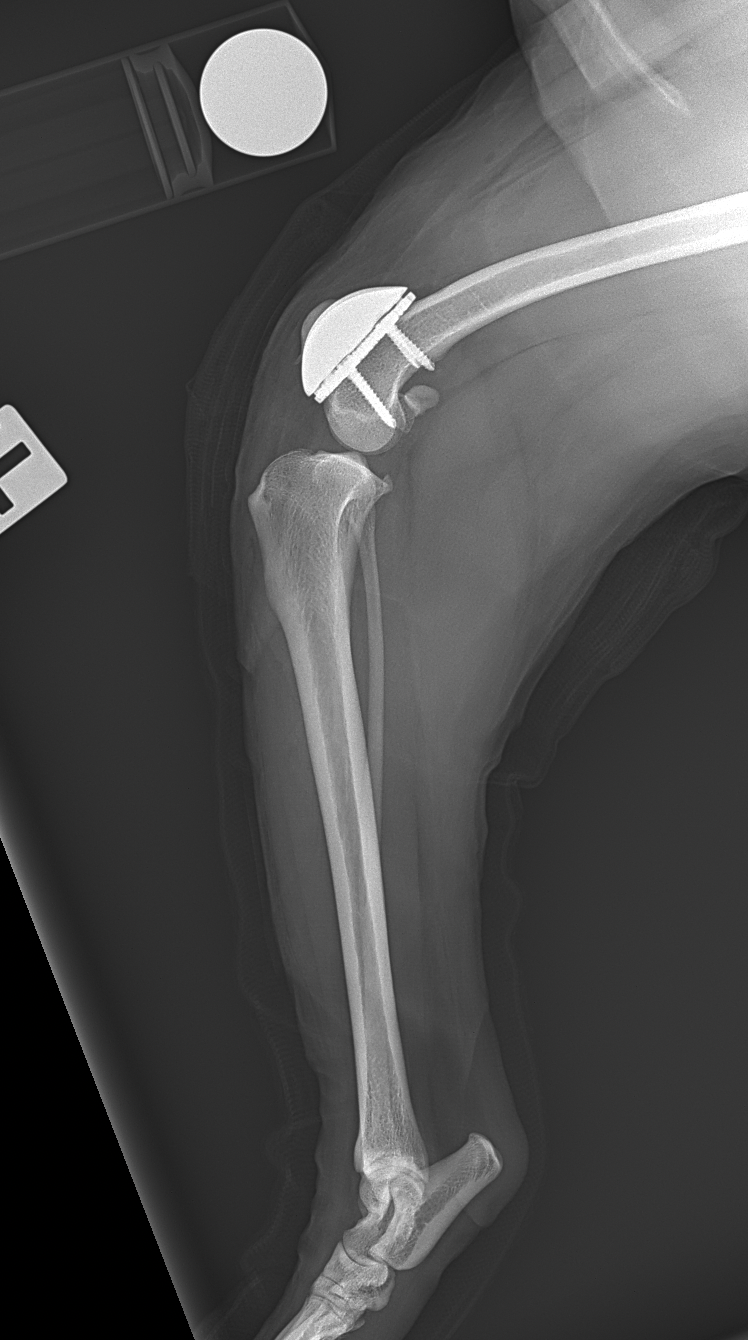

膝蓋骨内方脱臼に伴い慢性の異常な刺激が進行し、骨関節炎を認め関節軟骨はすでに不可逆的な変性を呈しています。多くの外科手術は”整復”を目的としますが、関節炎が進行した関節においては、単なる整復だけでは痛みや機能障害は残り続けます。そこで必要な手技は”再建”です。損傷した関節面をそのまま使うのではなく、人工滑車(PGR)を用いて新たな滑走面(DLC)を構築することで、関節内の異常なストレスを減少させ、除痛と機能回復を図ります。HAコーティングのベースプレートと骨がオッセオ・インテグレーションを起こすまでは安静が必要です。